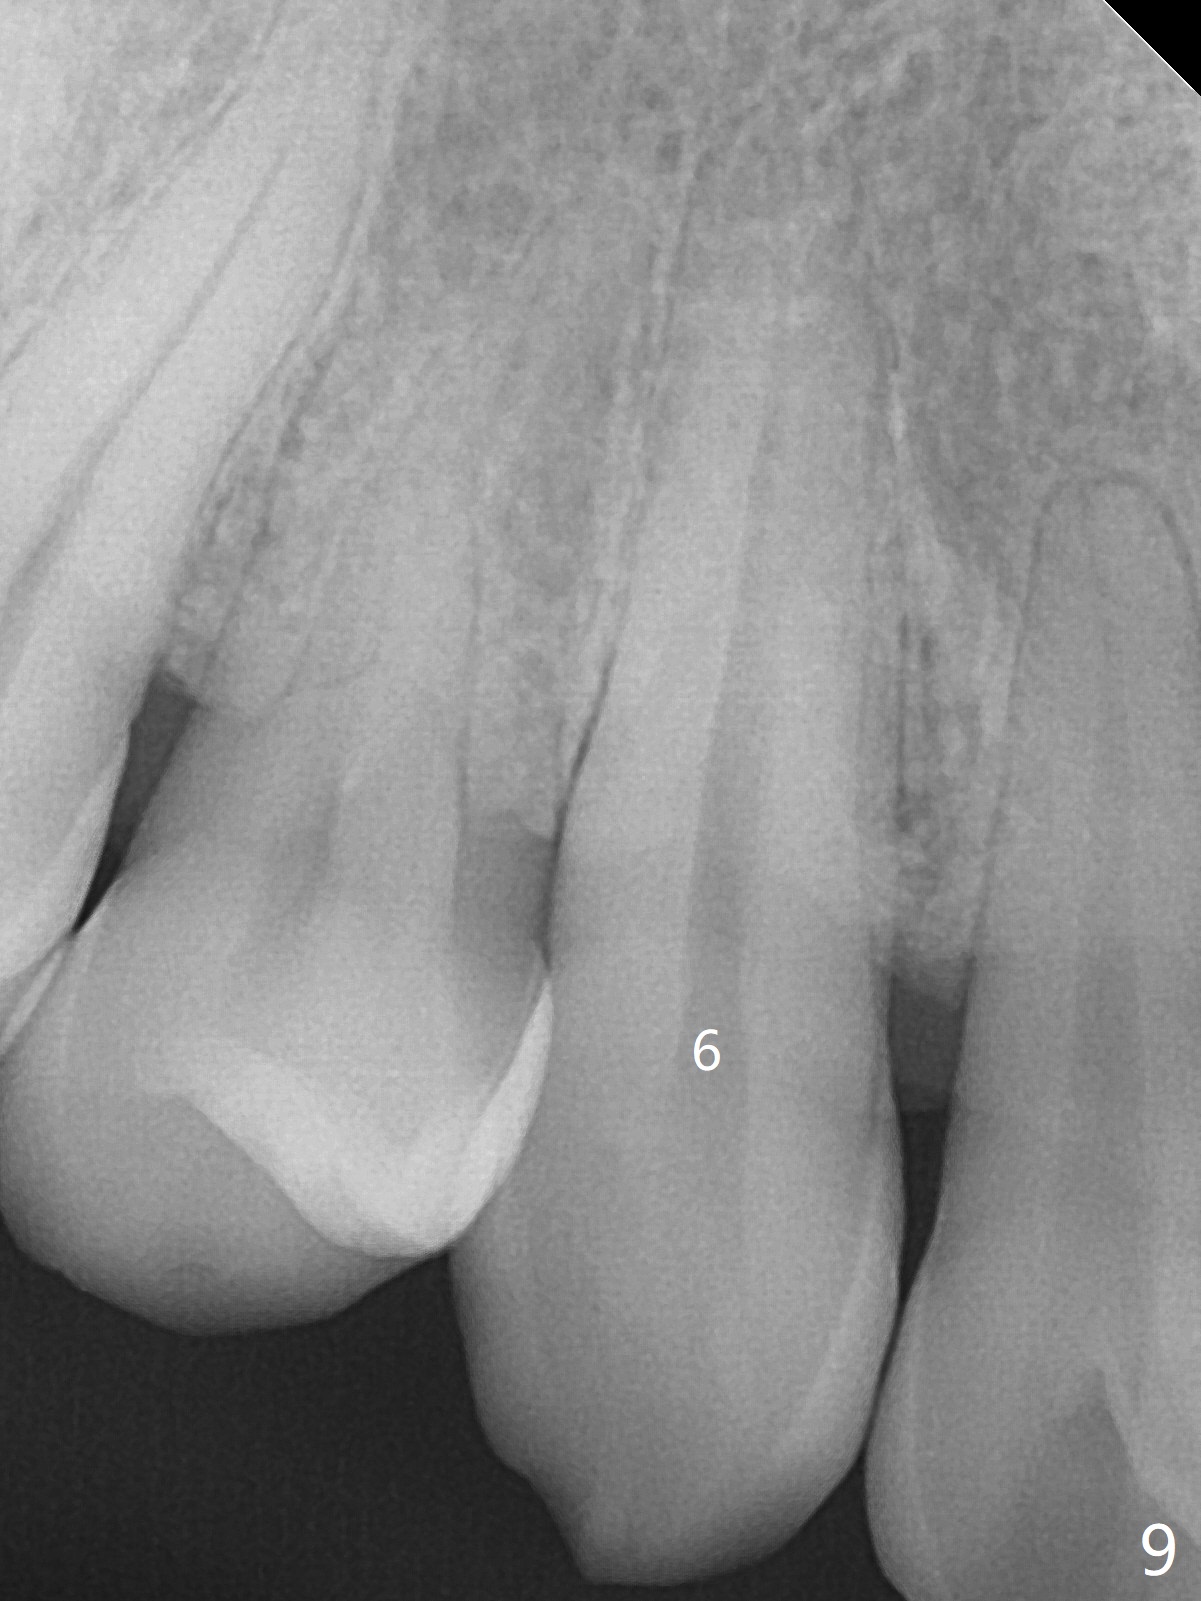

A 45-year-old man had severe malocclusion and chose non-extraction orthodontic treatment (Fig.1 (2012)). Five years later, the tooth #11 discolors (Fig.3, as compared to #6 in Fig.2). Immediately after RCT (Fig.4,5), the affected tooth has sudden change in shade (Fig.6). Two weeks later there is rebound in shade (Fig.7). The latter improves after two rounds of chair-side internal bleaching with 35% Hydrogen Peroxide for 20 minutes and build-up with the lightest shade composite (Fig.8). For optimum, place the bleach gel in the pulpal chamber and close the access with Cavit for a few days. In fact the latter is unnecessary. The treated tooth looks as normal as the tooth on the other side 1 year 10 months post whitening (Fig.9). PARL reduces 3 years post RCT (Fig.10 <, as compared to Fig.5).